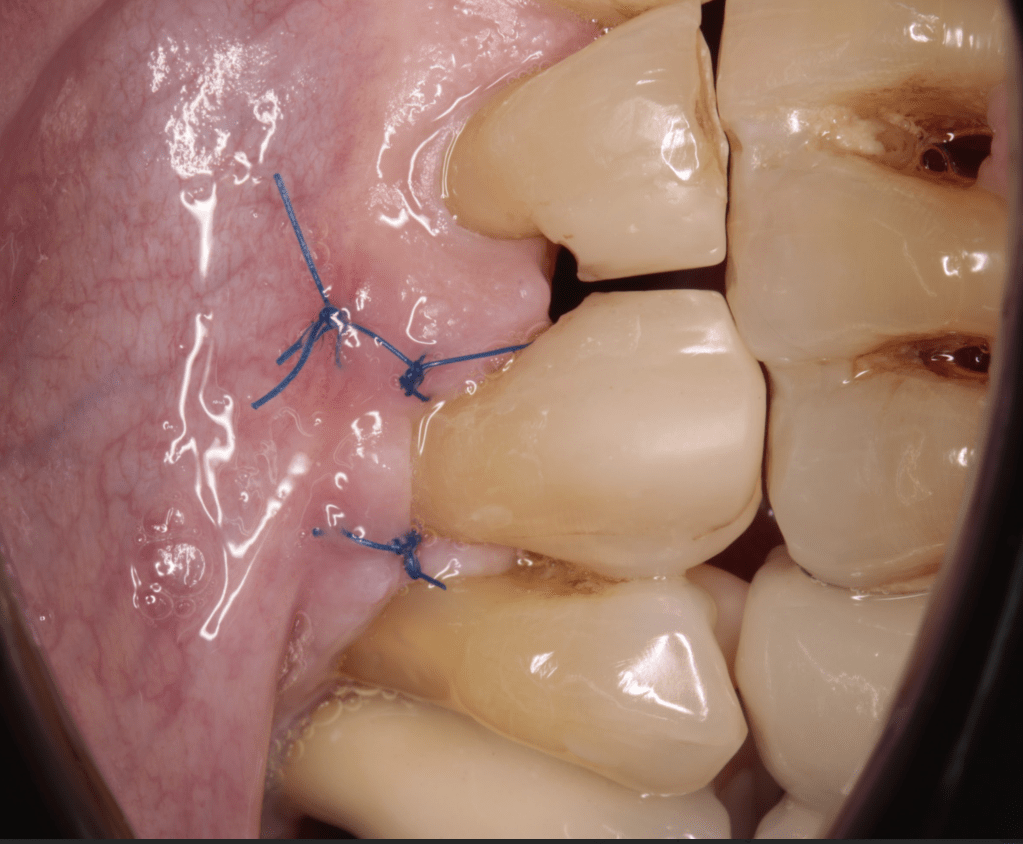

Gingivectomía +reco preendo +reconstrucción

Reco pre-endo gingivectomái, pared yuxtaosea

Reco preendo + gingivectomía